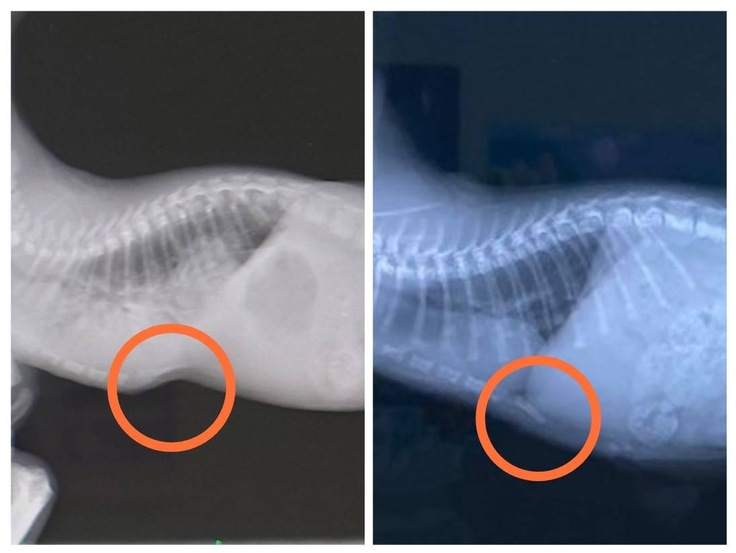

ナイトの漏斗胸ですが、マッサージの甲斐もありほとんどわからないぐらいまで治りました。ただ一度歪んだ(凹んだ)骨は凹みがなくなっても少し外側に反ってしまっています。今のところ特に日常生活には問題はありません。今後もしっかり観察していこうと思います。